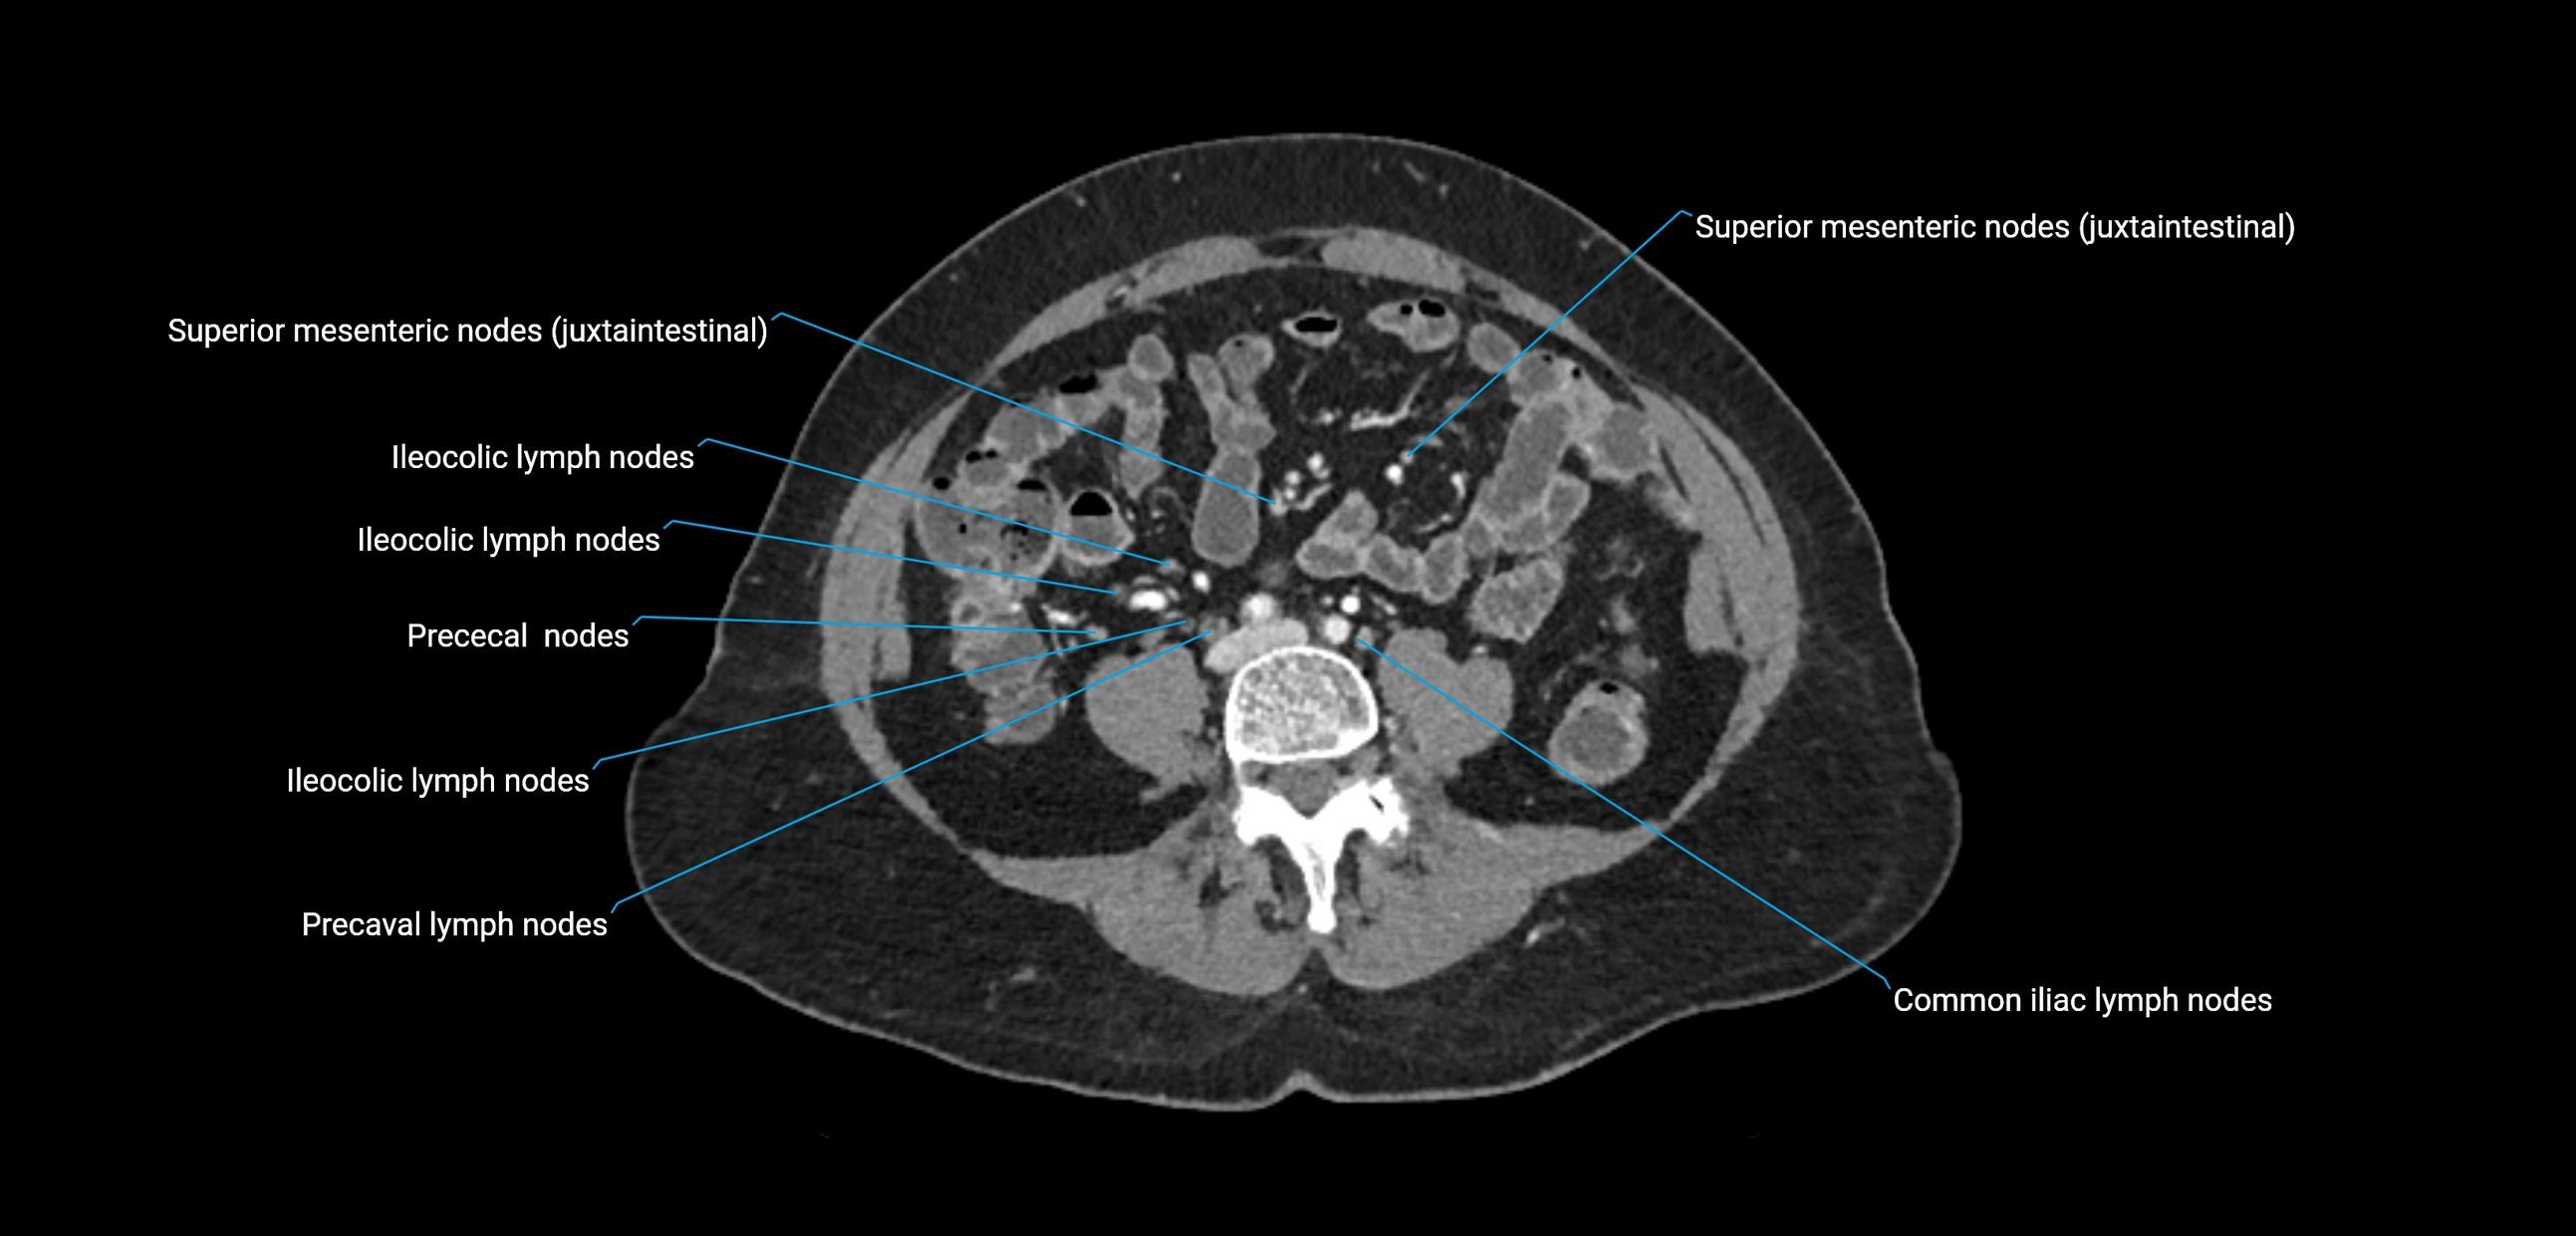

CT Appearance

CT Pre-Contrast:

• Nodes appear as soft-tissue density nodules adjacent to the aorta and IVC

• Calcification may be seen in chronic infections (e.g., tuberculosis)

CT Post-Contrast:

• Normal nodes enhance homogeneously

• Malignant nodes may show heterogeneous enhancement, central necrosis, or conglomerate formation

• Size >1 cm short axis is suspicious, though morphology and distribution are equally important